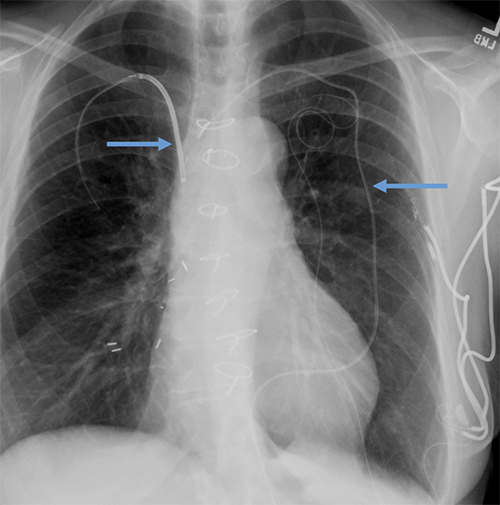

- CEID images with lead types:

Abandoned leads